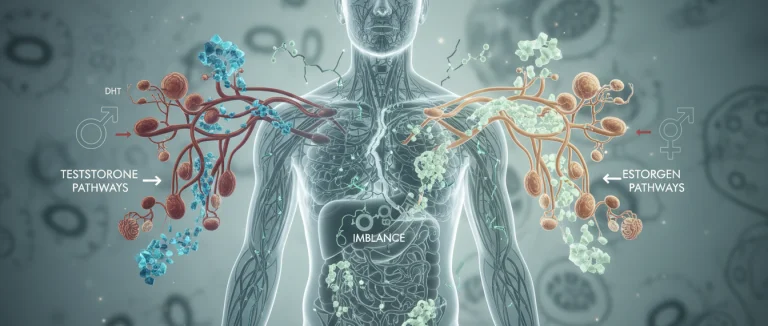

преимущества терапии